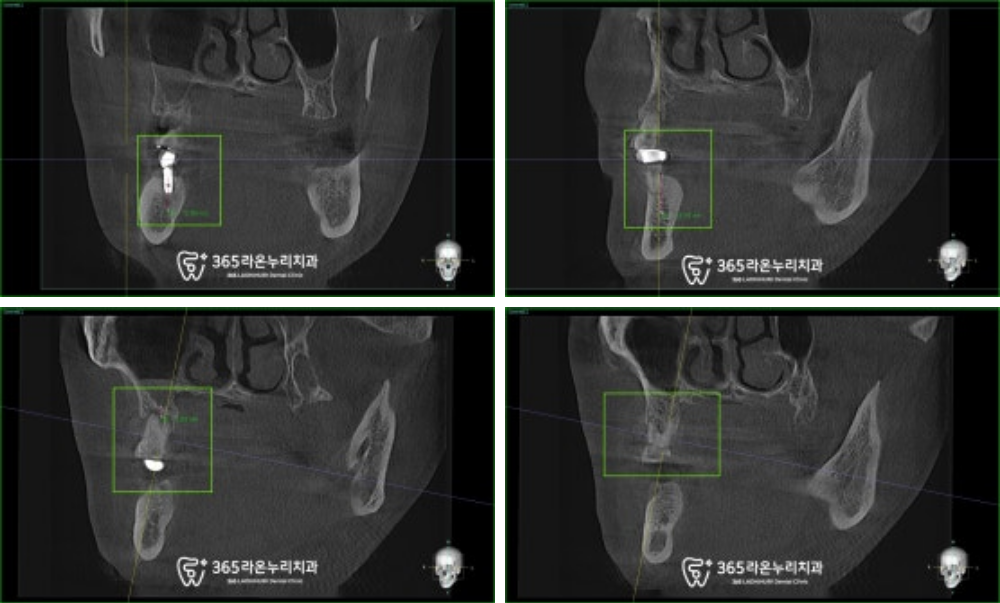

안전한 위치에 잘 심을 수 있도록

CT를 찍어 그 깊이를 확인해 보니

어느 정도 높이는 확보가 되나

일부 뼈가 부족한 곳은

골이식을 추가로 시행하기로 했습니다.